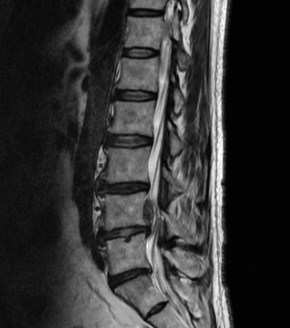

허리디스크는 디스크가 터져서 신경을 누를 경우 생기는 것으로 보통 4,5번에서 많이 발생하고 디스크가 터진 양이 적다면 터진 순간부터 수분이 날아가면서 양이 많이 없어지는데 그렇지 않고 양이 많을 경우 극심한 통증이 생깁니다.

통증이 덜한 환자들은 재활 , 물리, 약물치료 등을 통해 진행하지만 특정 원인이나 흘러나온 디스크가 신경을 많이 눌러 극심한 통증이 있다면 빠른 수술을 진행하는 것이 좋습니다.

허리디스크를 정확하게 진단하기 위해서는 엑스레이로는 힘들며, MRI를 통해 검사해야 정확하게 볼 수 있습니다.

MRI가 몸에 좋지 않지만 허리 통증으로 엑스레이만 진행 할 경우 오진이 많아 지속적인 통증이 계속 된다면 허리디스크를 의심하고 MRI 검사를 한번 받아보시길 권유드립니다.